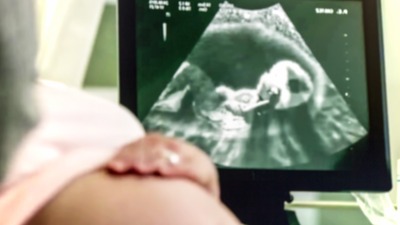

DHA'nın haberine göre, tüp bebek tedavisinin kısırlıkta en başarılı, gebelik oranı en yüksek yöntem olmasına rağmen gebelik şansının ortalama yüzde 50 civarında olduğunu kaydeden Prof. Dr. Faruk Buyru, "Yüzde yirmi civarında gebelik kaybı ve düşük olasılığını da göz önüne alınca eve bebek götürme oranı yüzde kırkın altına düşmektedir. Yani tedaviye başlayan çiftlerin yarıdan fazlası ilk denemede başarılı olamamaktadır. Bu durumu baştan gözönünde bulundurup, tedavi başarısızlığında ümitsizliğe kapılmamak gerekir" diye konuştu.

Tüp bebek başarısızlığını ikiye ayırmanın mümkün olduğunu vurguluyan Prof. Dr. Buyru; "İlk grup embriyo kalitesi iyi olduğu halde gebe kalamayanlar, ikinci grup ise embriyo kalitesi çok iyi olmadığı için gebe kalma şansı düşük olanlar. İlk grupta yani embriyo kalitesi iyi olanlarda sonraki denemelerde gebelik şansı daha fazladır. Tedaviyi gözden geçirip tekrar deneme yapıldığı takdirde büyük olasılıkla mutlu sona ulaşılacaktır. Embriyo kalitesinin çok iyi olmaması o aya özgü bir durum olabilir ve sonraki tedavilerde bazı değişikliklerle daha iyi embriyolar elde edilebilir. Ama üst üste kötü embriyo oluşması durumunda tedavide ısrar etmek doğru değildir. Problem sperm veya yumurta kalitesi ile ilişkili olabileceği gibi, gebeliğin yerleştiği rahim içi ile de ilgili olabilir. Yine tiroid veya şeker hastalığı gibi problemlerin bulunması, obezite, sigara kullanımı gebelik şansını azaltan faktörlerdir. Rahim ile ilgili şekil bozuklukları, tüplerde sıvı birikimi, miyom ve polipler tüp bebek tedavisi öncesinde değerlendirilip düzeltilmesi gereken problemlerdendir" dedi.